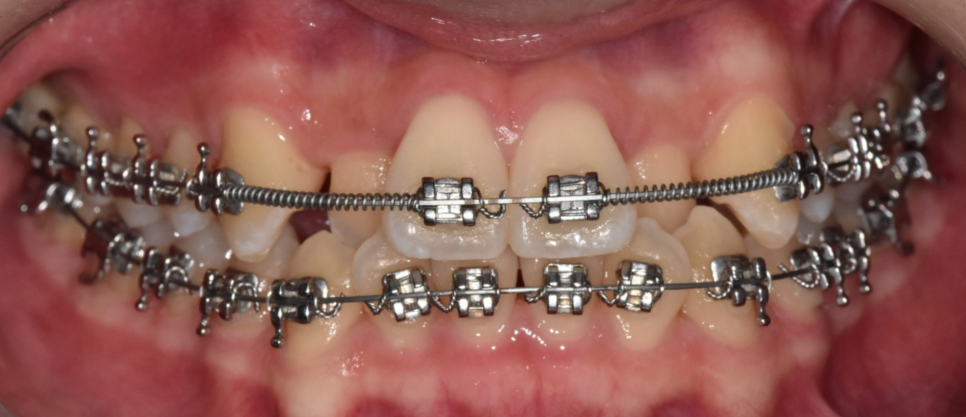

덧니를 치료하는 방식은 교정, 보철과 같은 치료가 있습니다.

보철의 경우 앞니에만 한정적이라면

고민해볼 수 있겠으나

교합까지 문제가 있는 경우

치아를 전반적으로 이동 시켜

재배열해주는 치아교정이 추천됩니다.

250616

상일동 치아교정에서는 다음과 같은 방법이 활용됩니다.

치아 상태, 환자분 연령을 고려

부분 교정, 전체 교정

발치를 해야할지 비발치로 진행할지

투명 교정을 할지 브라켓을 붙이는 철사교정으로 할지 말이죠.

덧니의 정도에 따라 선택지가 다르기 때문에,

정밀 진단이 꼭 필요합니다.